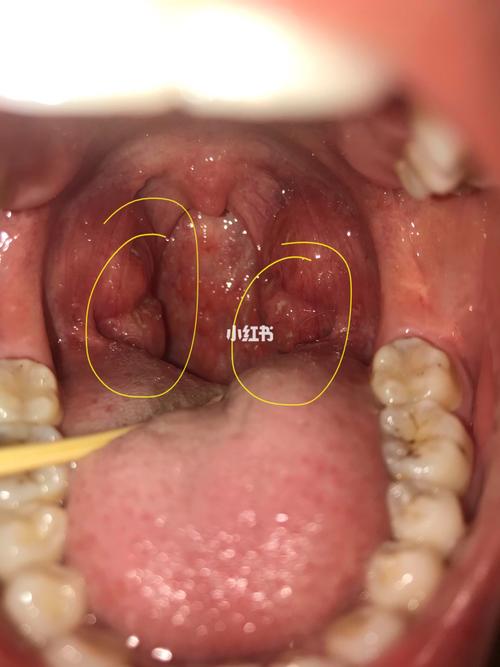

正常扁桃体图片结石

正常扁桃体图片结石,扁桃体图片正常的图片

扁桃体结石图片

扁桃体结石图片实拍

扁桃体结石图片症状

扁桃体结石

扁桃体结石实拍

扁桃体结石位置

扁桃体结石症状